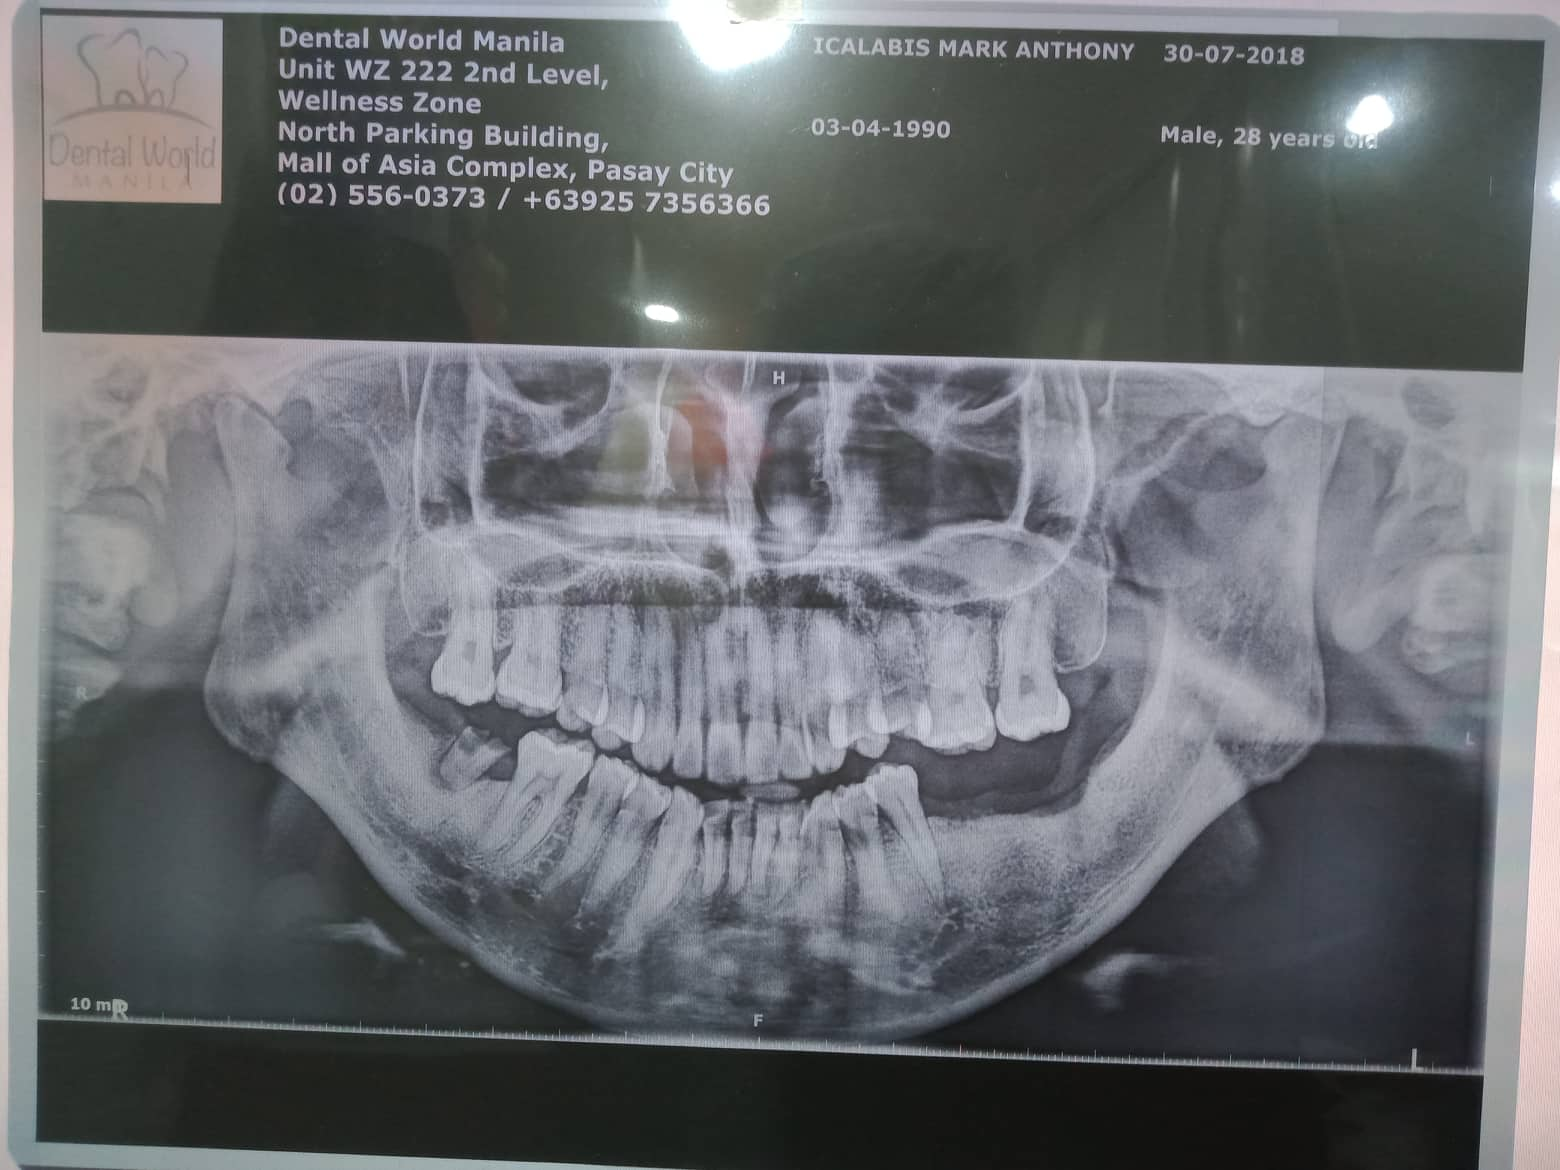

Edit Record Check our patient data records. Add patient information Patient Info Profile picture Last Name First Name Middle Name Birthdate Age Street Barangay City Country Zip Code Contact number Email Procedure 07/31/21 adj 16x22 UL 09/24/21- removal of lower braces exo 46/ upper adjustment chain 10/23/21- removal of braces upper and lower (for resto: 36/37/47 RCT #11- open canal 26mm= camphenol 11/3/21- 26mm yellow and white file apexcal composite veneer #11 11/08/21 - red file/ laser RCt tx for obturation next meeting 11/13/21 - obturation 26mm with restoration lingual pit 03/5/22- LC 26 Lingual pit, Occ/ Op File icalabisrct11.jpg File 2 301088955_824076712092412_6089268001725499639_n.jpg File 3 301583710_588567209482622_936847165020659250_n.jpg File 4 301875545_1490603051363326_3867455551585293159_n.jpg File 5 302308769_1073326889984866_975291161993186277_n.jpg File 6 File 7 File 8 File 9 File 10 File 11 File 12 File 13 File 14 File 15 File 16 File 17 File 18 File 19 File 20 Retain Record Retain Record Yes No Save Your Changes